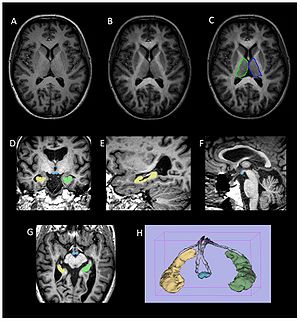

|

The regions-of-interest (ROIs) were manually drawn by an experienced radiologist by using the b 1000 images, averaged for all measured directions, the FA maps and the proton-density weighted images. For that purpose, the maps of ADC, FA, R2 and R2* as well as the proton-density weighted images were first co-registered. The ROIs were segmented by syncing the b 1000 images, averaged for all measured directions, the FA maps and the proton-density weighted images in ImageJ. The ROIs were stored in the ROI manager and transferred to the co-registered maps. The segmented brain regions were highlighted in different colors: CN—black; PU—red; GP—green; TH—white; SN—blue; CC—cyan. The diffusion-weighted images, the R2 and R2*-weighted maps were transferred to the 3D Slicer software in order to co-register the R2 and the R2* maps as well as the MD and the FA maps |